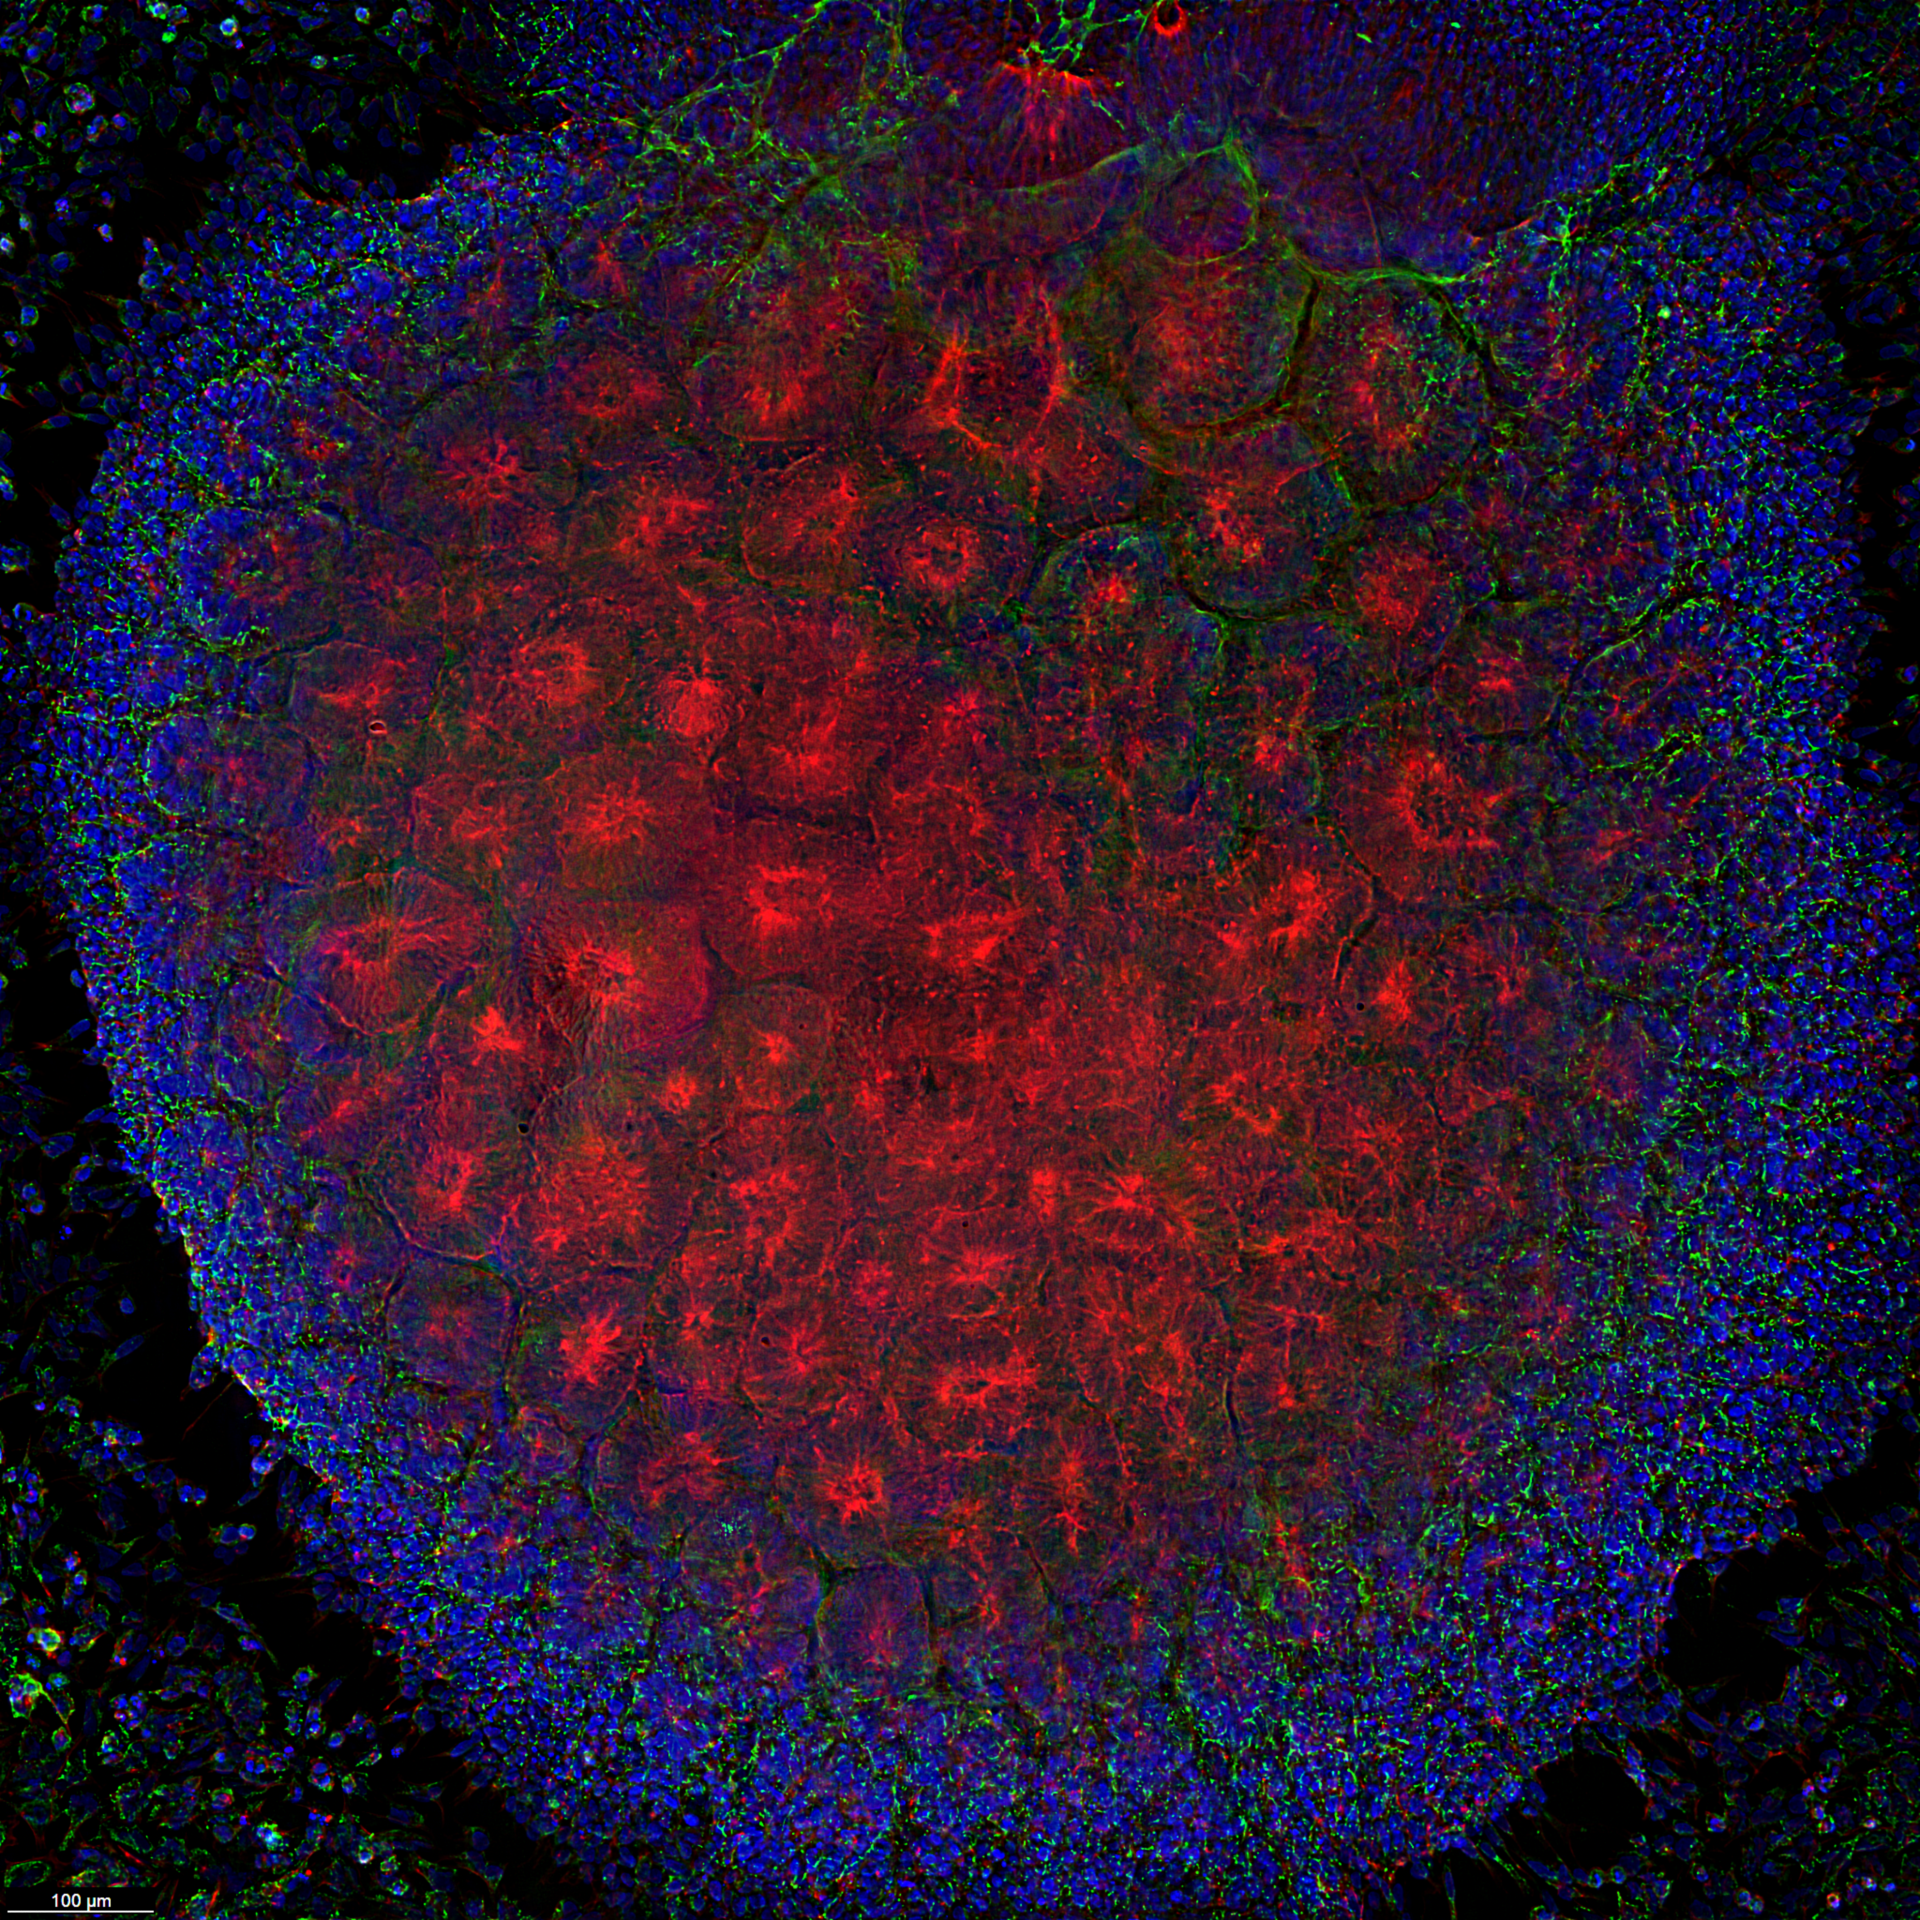

Our research focuses on the developmental and genetic mechanisms behind a cellular transformation in pediatric rhabdomyosarcoma. Through our research, we aim to ultimately uncover novel therapeutic vulnerabilities to treat rhabdomyosarcoma. Investigators have long believed that rhabdomyosarcoma develops solely from genetic insults to developing muscle progenitor cells. In children, however, rhabdomyosarcoma can be found all over the body in tissues that are devoid of skeletal muscle – like the salivary glands, biliary tree, omentum, and the bladder, among other parts of the body.

Through genetic fate mapping in genetically engineered mouse models, our laboratory revealed that rhabdomyosarcoma in children can originate from endothelial progenitor cells and not solely from muscle progenitor cells. This research revealed that there is a cell reprogramming event that transdifferentiates the transforming cells. Specifically, we found that some cells that are committed to becoming endothelial cells get reprogrammed to become a myoblast-like cell or rhabdomyosarcoma.  Our laboratory is studying the mechanisms that underlie this cell reprogramming event and what dictates that cell fate decision. As well, we seek to determine how the cellular origin dictates the location of these tumors and how that origin ultimately predicts patient survival.

Our rhabdomyosarcoma research involves a number of internal and external collaborations and includes techniques and methodologies like the development of unique mouse models, the use of human primary and rhabdomyosarcoma cell lines, patient-derived xenografts and induced pluripotent stem cells. To advance our research, our laboratory also uses resources like applied bioinformatics, gene editing, transgenic mouse generation, light microscopy, and flow cytometry.